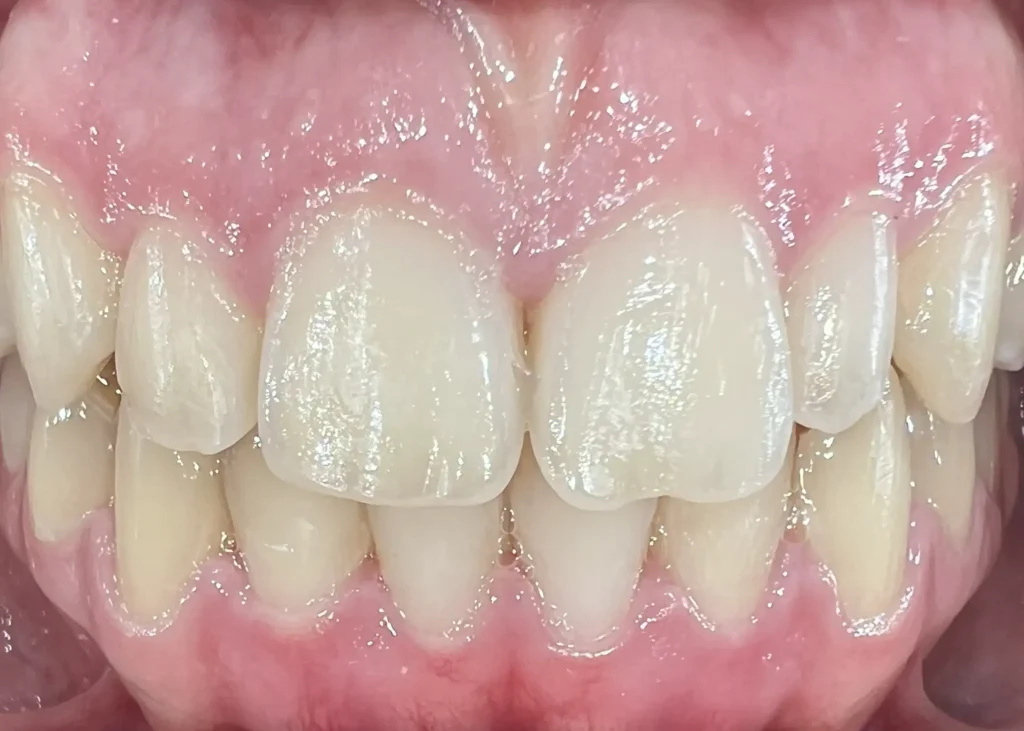

Casos clínicos de ortodoncia en CDPA